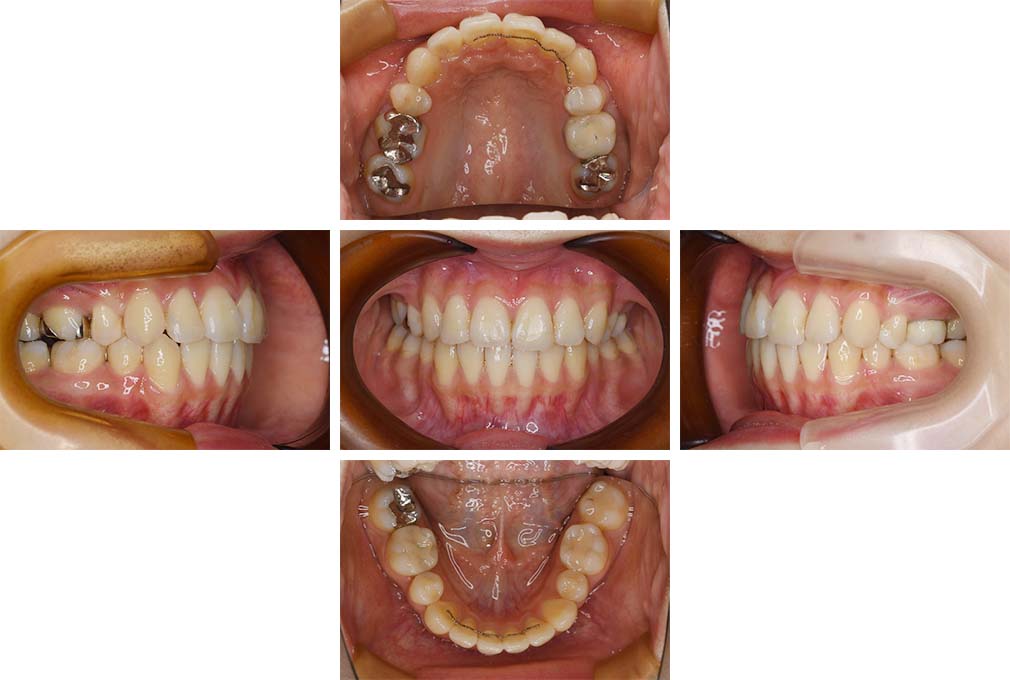

CASE:01

叢生を伴う骨格性上顎前突

初診時年齢 15歳10カ月

性別 男性

上顎前歯の前突と叢生を主訴として来院された。大臼歯関係は左右側ともにⅡ級で上顎の方が前方に位置していた。叢生を伴う骨格性上顎前突と診断し、上下顎小臼歯抜歯を行っていただきマルチブラケット装置に顎外固定装置を併用して動的治療を行った。顎外固定装置や矯正用ゴムの使用など協力状態も良好で、動的治療期間2年0カ月、調整来院20回でマルチブラケット装置を撤去し保定へ移行した。動的治療終了後10年0カ月を経過したが保定移行時とほぼ同様の咬合状態で良好な状態を保っていた。

治療前

15歳10か月

治療後

動的治療期間2年0カ月

18歳5か月

10年経過

動的治療終了後10年0カ月

28歳5か月